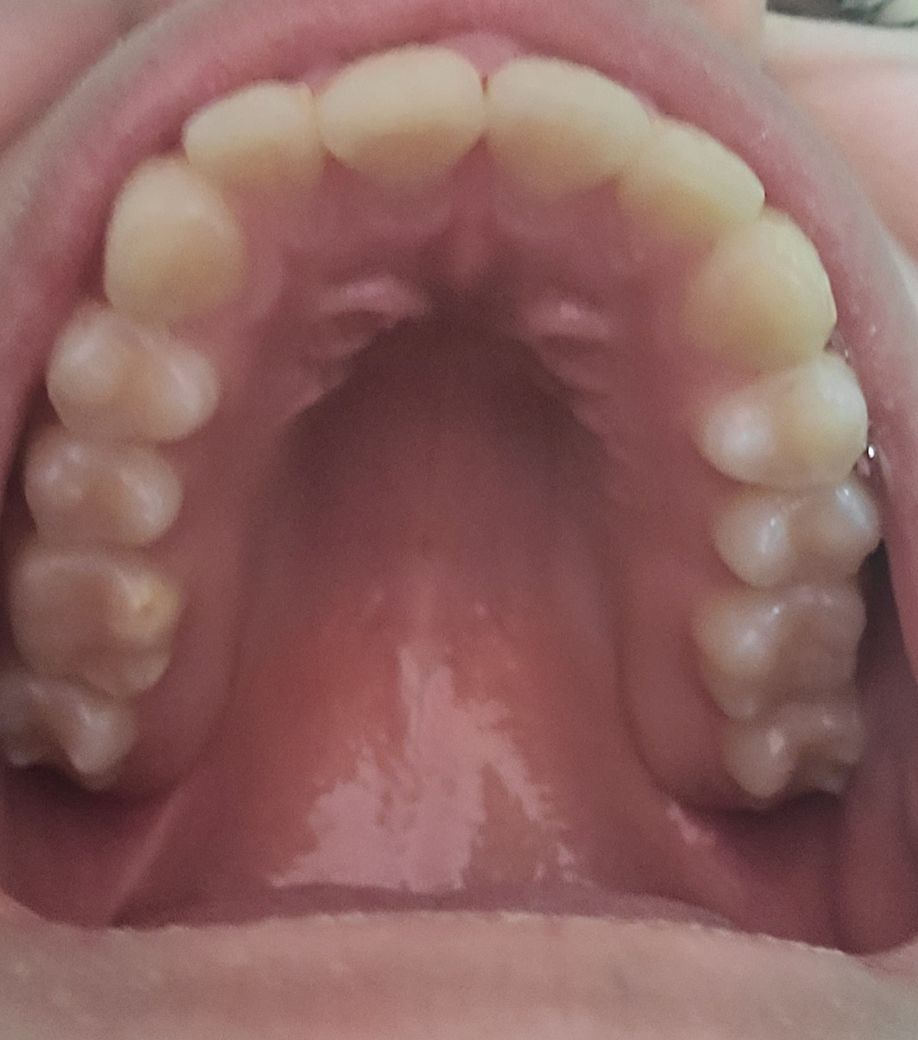

윗니 유지장치 안했는데 많이 휘었나요? (사진주의))

윗니는 고른편이고 아랫니가 심했어서 아래만 하려다가 위도 같이 하게 됐습니다. 때고 나서 아랫니는 고정된 유지장치를 했고 위는 빼고 끼는 유지장치로 받았습니다.

첫몇달은 잘끼고 다녔지만 불편하고 자주 까먹어서 이제는 전혀 안끼고 다닙니다^^... 손가락으로 치아를 문지르면 치아간의 차이는 약간 느껴지지만 개인적으로 외관상 봤을때는 다를게 없어보여요. 물론 제가 전문가가 아니라서 뭐라고 할수는 없고 제 게으름에 반성해야하지만...

• 2번 째 사진

교정이 끝났을 때 초기 상태를 알 수 없기 때문에 유지 장치를 사용하고 난 다음에 치아가 얼만큼 이동했는지 확인하기 어렵습니다.

교정을 하고 나면 치아는 교정하기 이전으로 돌아가려고 하는 속성을 가지고 있기 때문에 가능한 유지 장치는 오래 끼고 있는 것을 권고하고 있습니다.

기존 치아배열이 어땠는지. 모르기에 답변에 한계가 있습니다. 크게 문제가 보이진 않습니다

사진상으로는 크게 문제가 되어 보이는건 없는거 같습니다. 그래도 유지장치는 착용을 하시는게 좋습니다.

다소 변형이 되고 있는 것으로 보이며, 유지장치를 착용하지 않는 경우치아가 서서히 움직여 변형이 오게되기에 유지장치를 잘착용하길 권합니다.